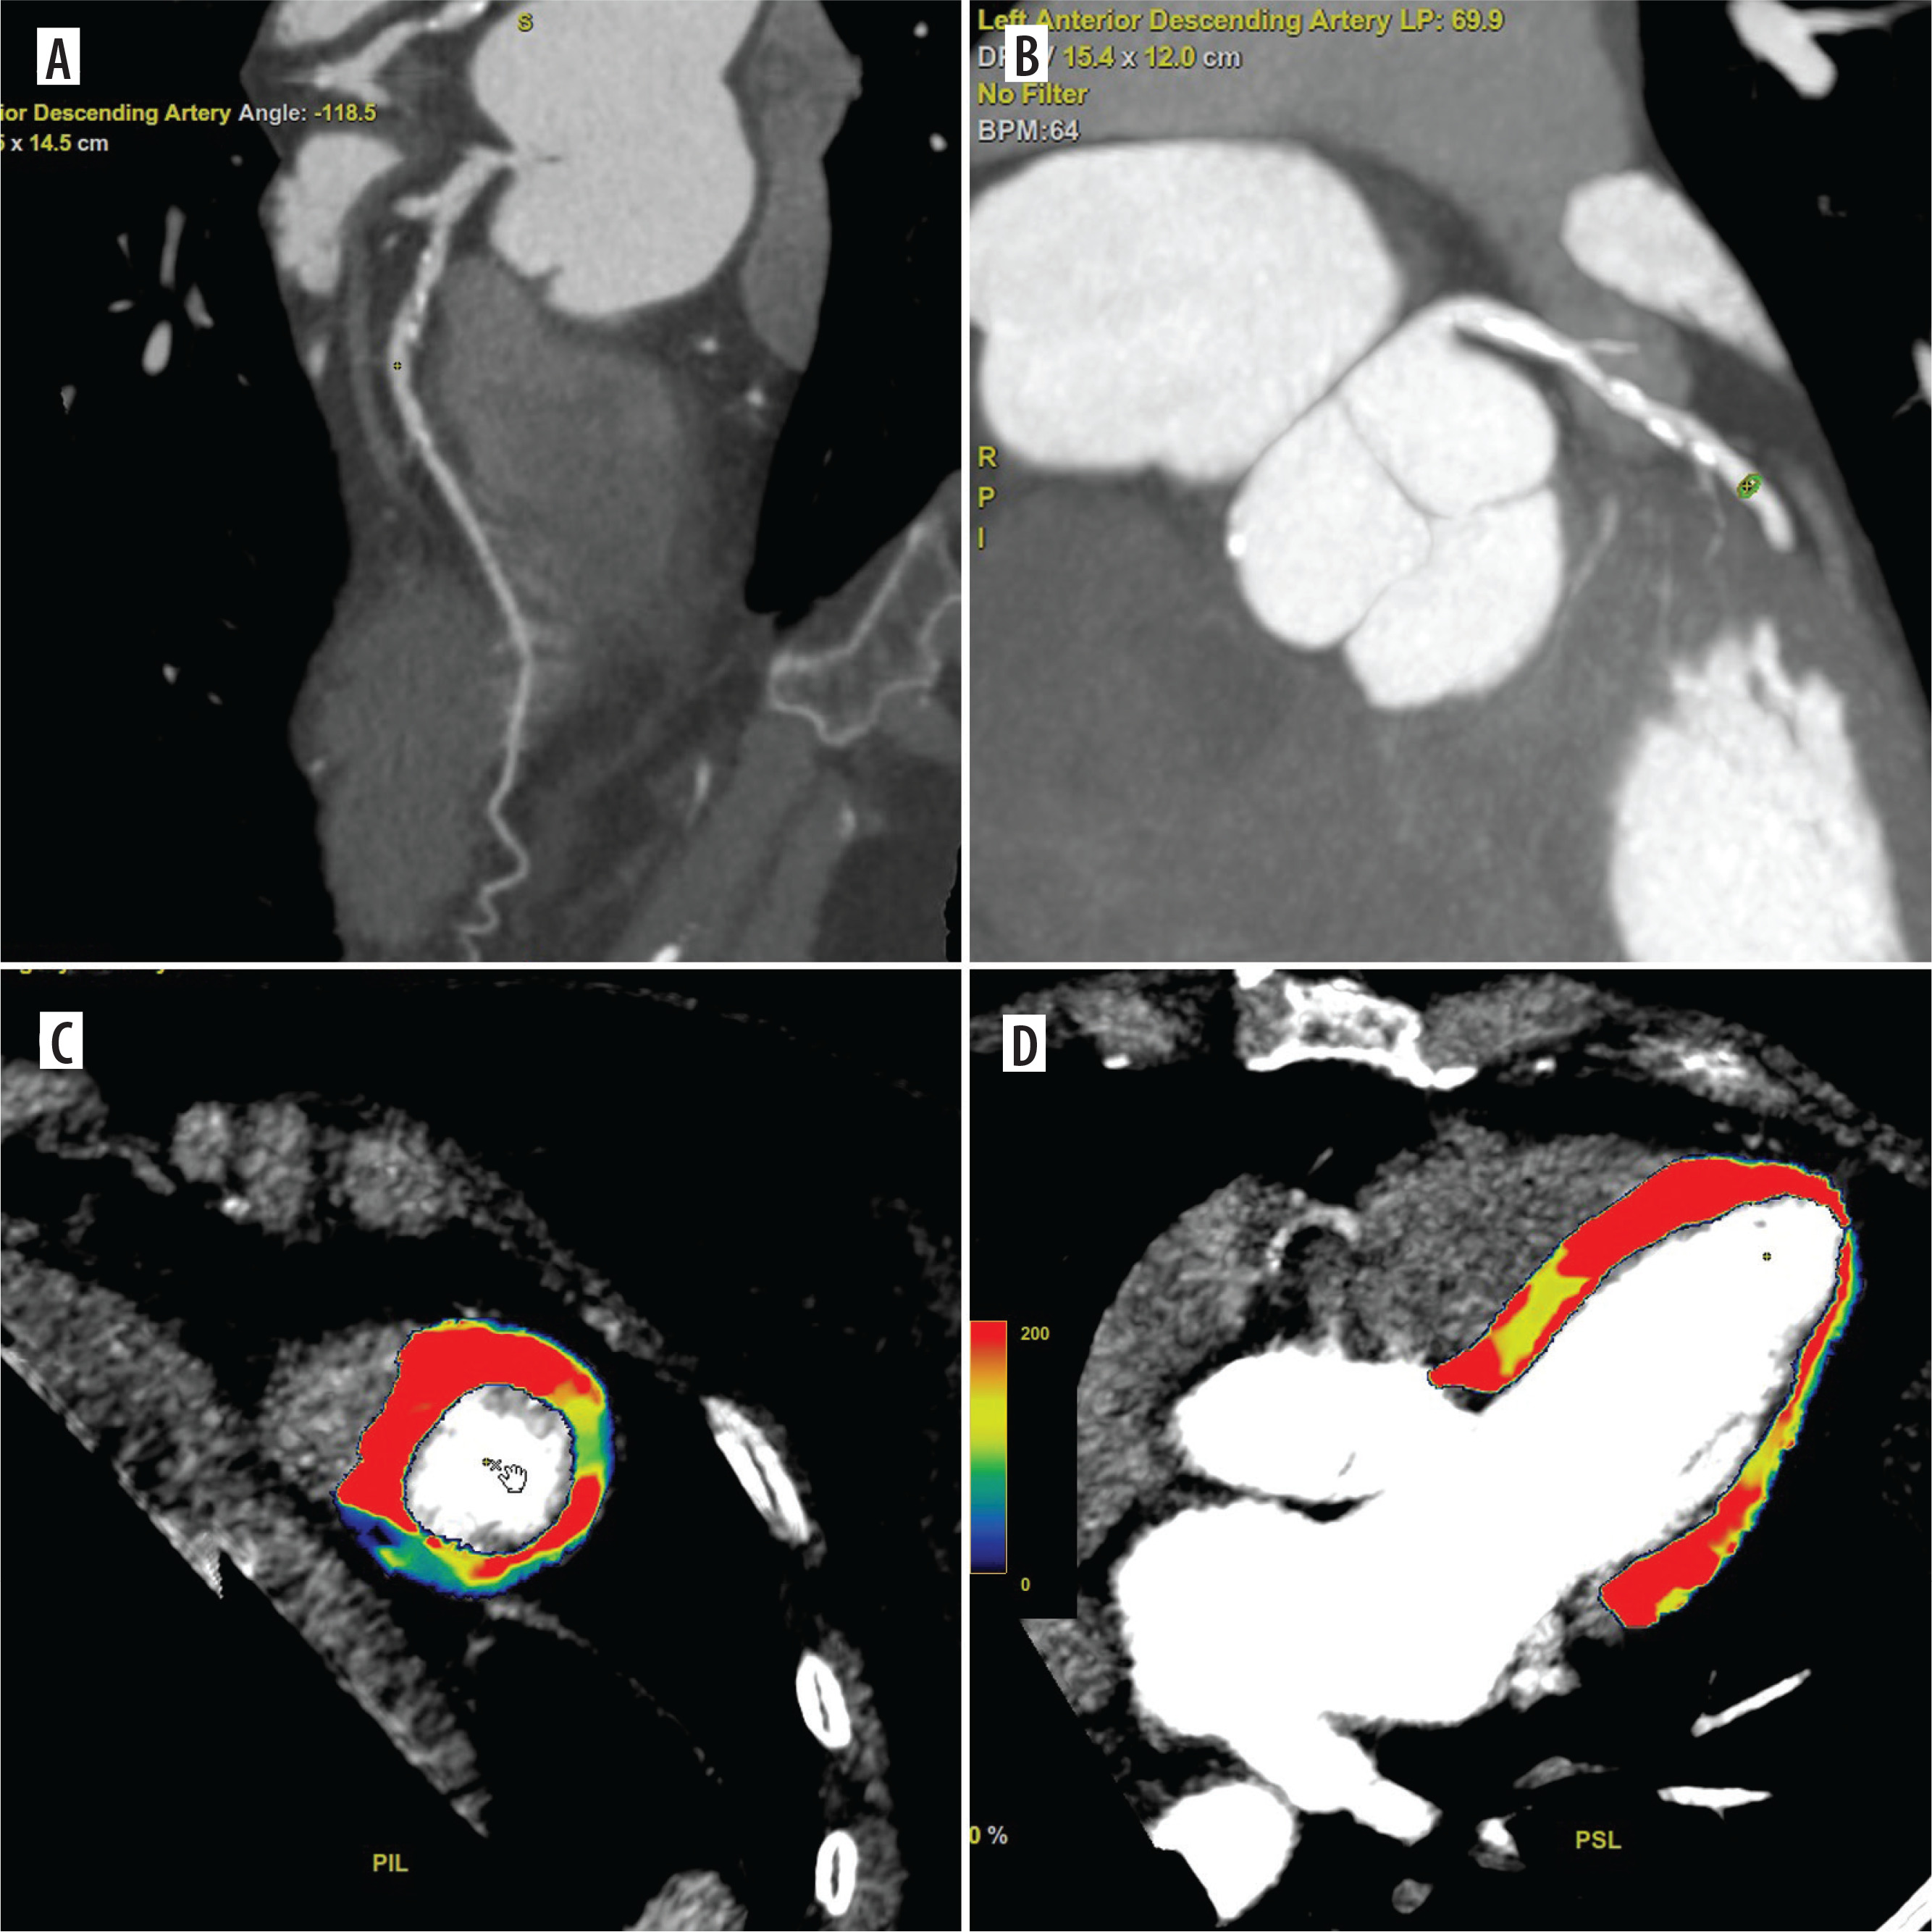

Figure 3

Coronary computed tomography angiography (CCTA) and dynamic computed tomography perfusion (CTP) scans from a 64-year-old female with non-specific chest discomfort and mild exercise intolerance. The patient underwent a comprehensive CT evaluation, including calcium scoring, CCTA, and dynamic stress CTP. CCTA revealed 30% stenosis in the left main (LM) and 50-60% stenosis in the left anterior descending artery (LAD) (A, B). Dynamic stress CTP with regadenoson showed reduced blood flow in the mid-anterior segment, apical anterior segment, and the border zone between the basal and mid-septal anterior segment (C, D). Based on the confirmed ischaemia, the patient was referred for invasive coronary angiography (ICA), which revealed 30% stenosis in the LM and a myocardial bridge in the LAD. The patient was deemed suitable for conservative management. Dynamic CTP Color-coding: Normal stress myocardial blood flow (MBF) is shown in red, and ischaemic regions (MBF < 100 ml/100 g/min) are depicted in blue